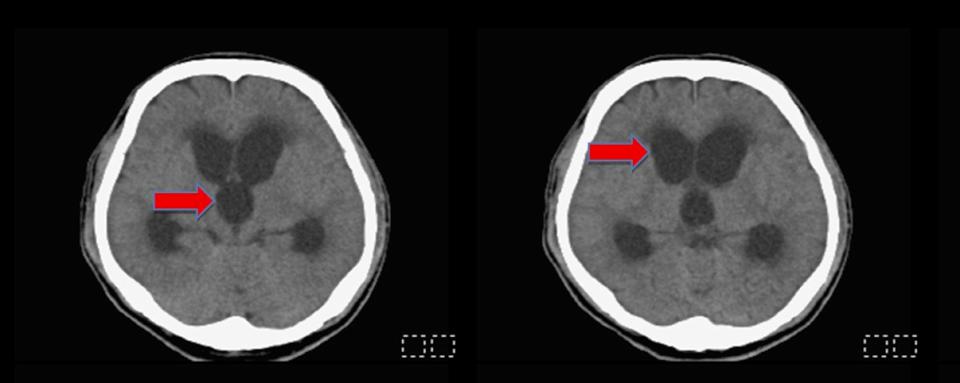

高市48歲男子從事油漆工作過程頭部外傷顱內出血,就醫未開刀治療入住安養機構,突發意識不清及嗜睡送至民生醫院急診,腦部電腦斷層檢查確認水腦症,接受腦室腹腔分流術排出多餘腦脊髓液,術後清醒,恢復正常行動。

陳志豪說,臨床可透過電腦斷層(CT)、磁振共振造影(MRI)判斷追蹤評估手術,根據研究適時分流腦脊髓液有助改善神經功能。圖/民生醫院提供、文/高培德